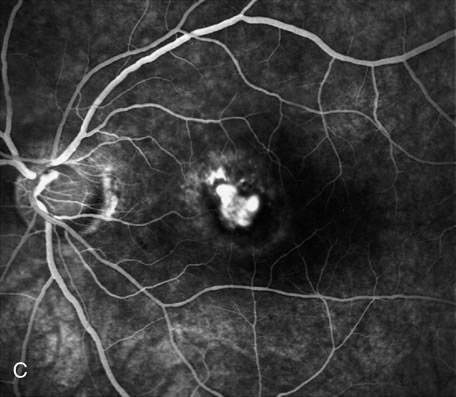

Fig. 5. A. Clinical photograph of a large, crescent-shaped rip of the retinal pigment epithelium (RPE) in the temporal macula. B. Early-phase fluorescein angiography study demonstrates the presence of a window defect corresponding to the RPE rip, which exposes the choroidal vasculature. Where the RPE is redundant in the central macula there is blockage of the normal choriocapillaris fluorescence. C. Late-phase angiogram reveals intense hyperfluorescence seen through the RPE defect.

Fig. 6. Classic, submacular choroidal neovascularization (CNV) and retinal pigment epithelium (RPE) rip. Fluorescein angiography reveals the presence of a well-defined subfoveal CNV and hyperfluorescent area in the inferior macula corresponding to the RPE rip (yellow arrow).